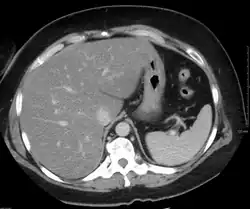

- компьютерная томография и магнитно-резонансная томография

При компьютерной томографии выявляется в разной степени выраженное диффузное снижение денситометрических показателей паренхимы печени (ниже 55 HU, иногда вплоть до отрицательных значений, соответствующих плотности жира), как правило отмечается увеличение размеров органа. Возможно выявление ограниченных участков жировой инфильтрации, окружённых неизменённой тканью печени. Чаще локальная жировая инфильтрация наблюдается в сегменте S4 печени, имеет довольно ровные, прямые контуры, ход сосудов в инфильтрированной жиром ткани не изменён, масс-эффект (объёмное воздействие на окружающие структуры) отсутствует.